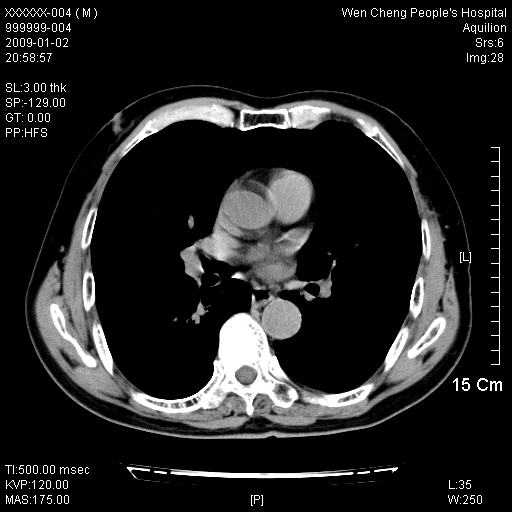

男性,73岁,有慢支病史,肿瘤系列标志物检验正常,血沉及血常规正常

右肺下叶背段小片状 磨玻璃样模糊影,内见血管及含气支气管像,支气管管壁增厚。考虑:慢性炎症!

1)不排除右肺下叶周围型肺癌可能;建议追踪复查。2)左右冠状动脉钙化。

右肺下叶背段小片状 实性与磨玻璃样影,内见血管及含气支气管像,支气管管壁增厚,边缘见长毛刺影。考虑:慢性炎症或肿瘤!建议抗炎治疗复查,密切观察随访!

右肺下叶片团状影内见扩张的含气支气管和支气管管壁增厚,其周有磨玻璃样模糊影和长毛刺。考虑慢性炎症可能性大。

2、右肺下叶片团状影内见扩张的含气支气管和支气管管壁增厚,其周有磨玻璃样模糊影和长毛刺。考虑周围型肺ca可能,结核不排。

高度提示细支气管肺泡癌,建议抗炎治疗半月观察病灶变化,如无明显改变,建议立即手术治疗.